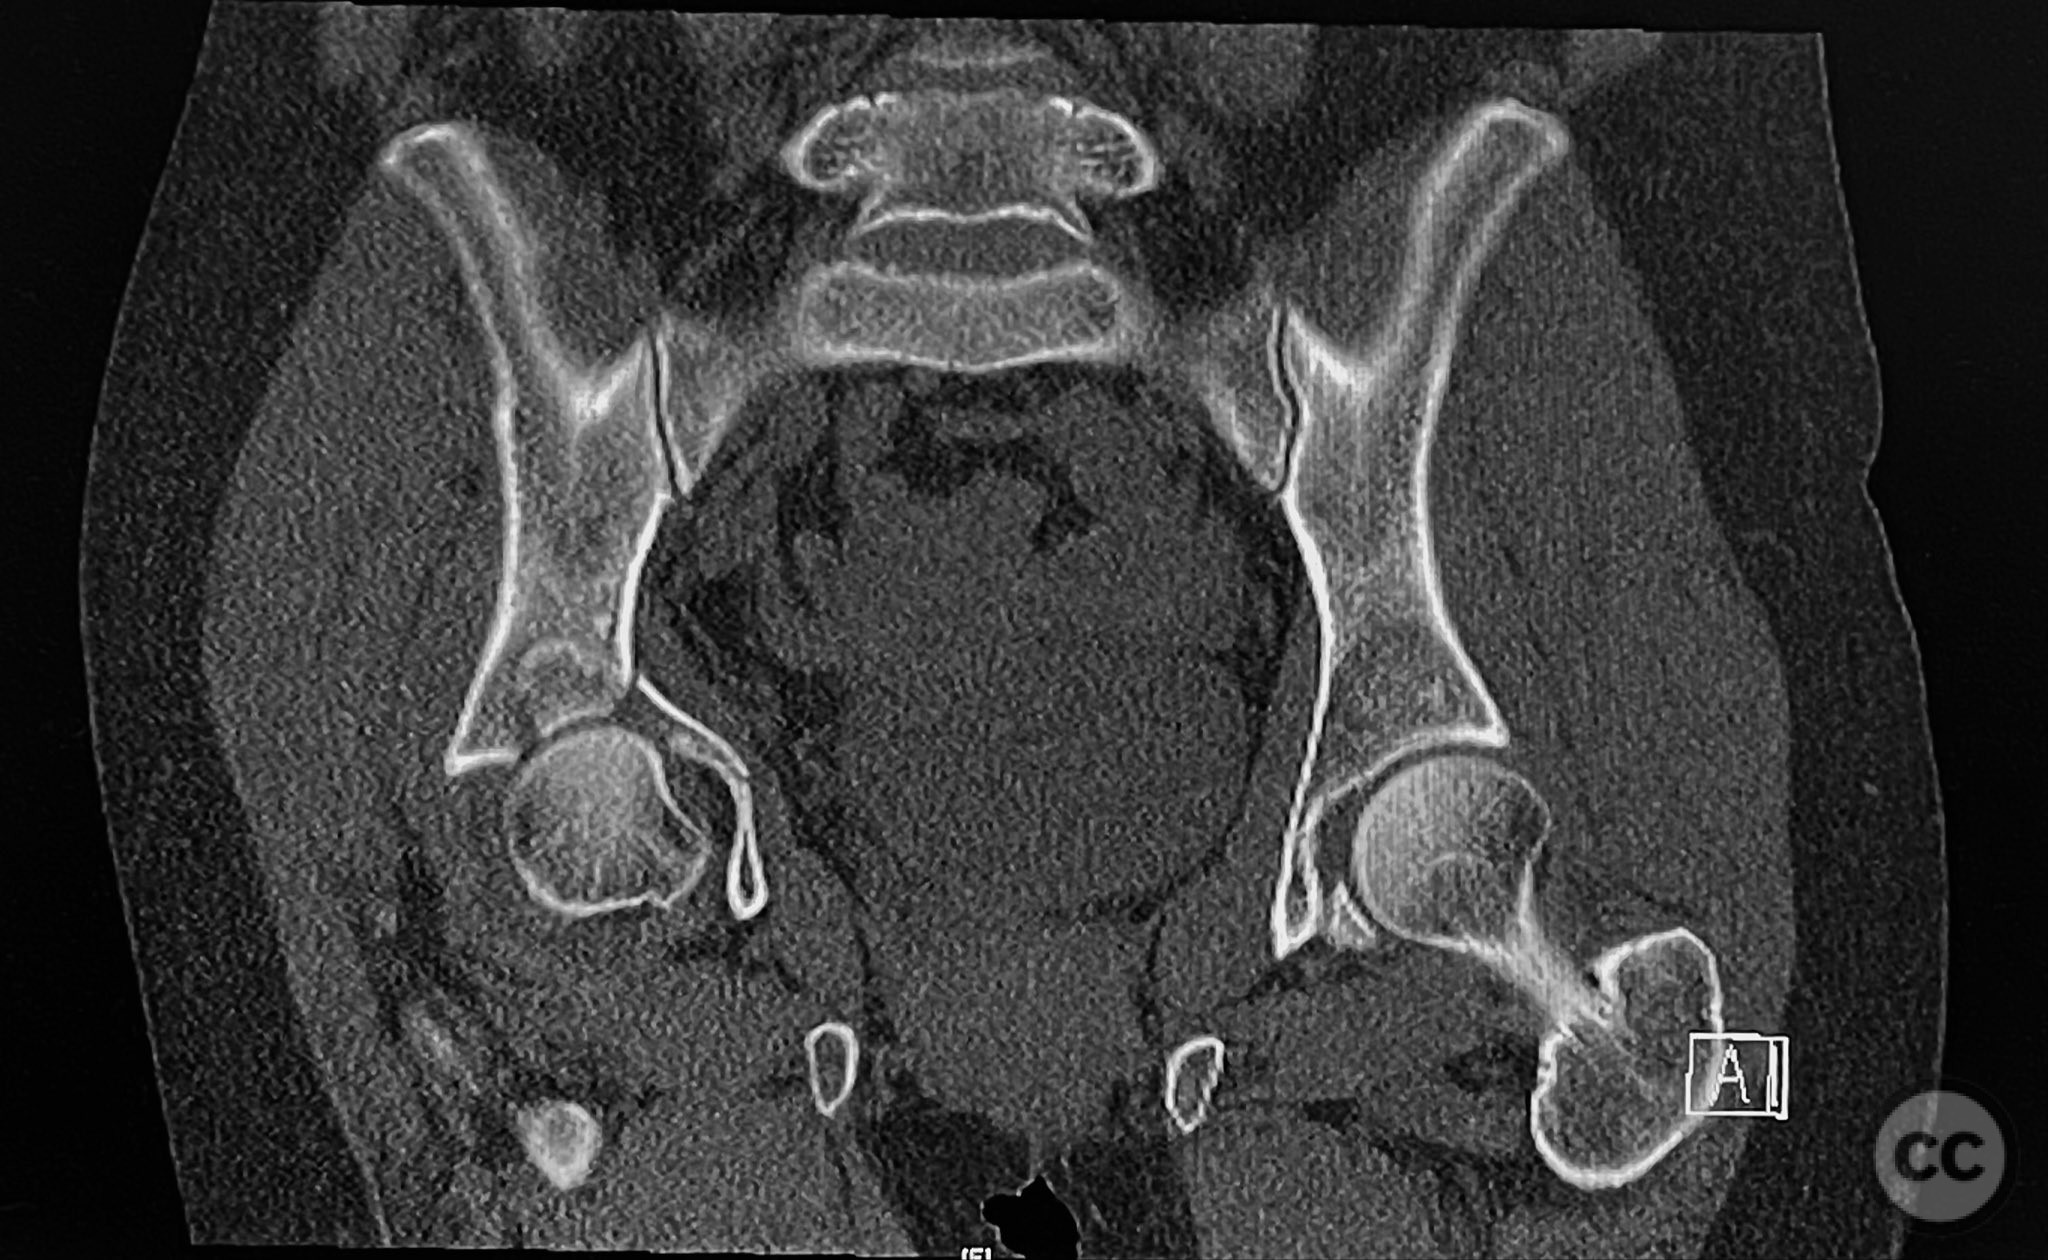

Clinical and radiological findings:  The patient sustained an acetabular fracture with a rare posterior medial dome impaction fragment, as demonstrated on AP pelvic radiographs obtained in skeletal traction. Surface renderings and axial CT images revealed multiple incomplete fracture lines, including a rhomboid-shaped cortical fragment adjacent and proximal to the anterior column/wall fragment. Coronal and sagittal reconstructions further delineated the impacted articular fragment and its relationship to the surrounding acetabular dome. The fracture pattern is classified as AO/OTA 62B3 (associated both-column fracture with dome impaction).